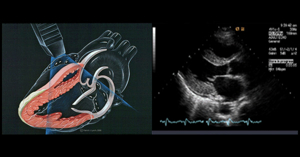

- 혈관 초음파로 혈관 구조를 확인하고 도플러를 통해 혈액의 흐름 방향, 속도, 역류 여부 및 역류 시간을 측정합니다.

- 이 검사를 통해 정맥 내 판막 손상 부위에서 혈액이 역류하는 정도를 평가하고, 정맥류의 원인이 되는 혈관을 정확히 찾아낼 수 있습니다.

- 일반 초음파의 원리에 도플러 효과를 적용한 검사로, 움직이는 혈액의 속도와 방향을 실시간으로 측정할 수 있습니다.

- 혈관 내 혈류의 특성을 분석해 혈류가 정상적으로 흐르는지, 역류나 협착이 있는지 평가할 수 있습니다.

- 혈관의 기능적 상태를 파악하는 데 중요한 역할을 하며, 하지정맥류, 동맥 협착, 혈전 등 혈관 질환 진단에 쓰입니다.